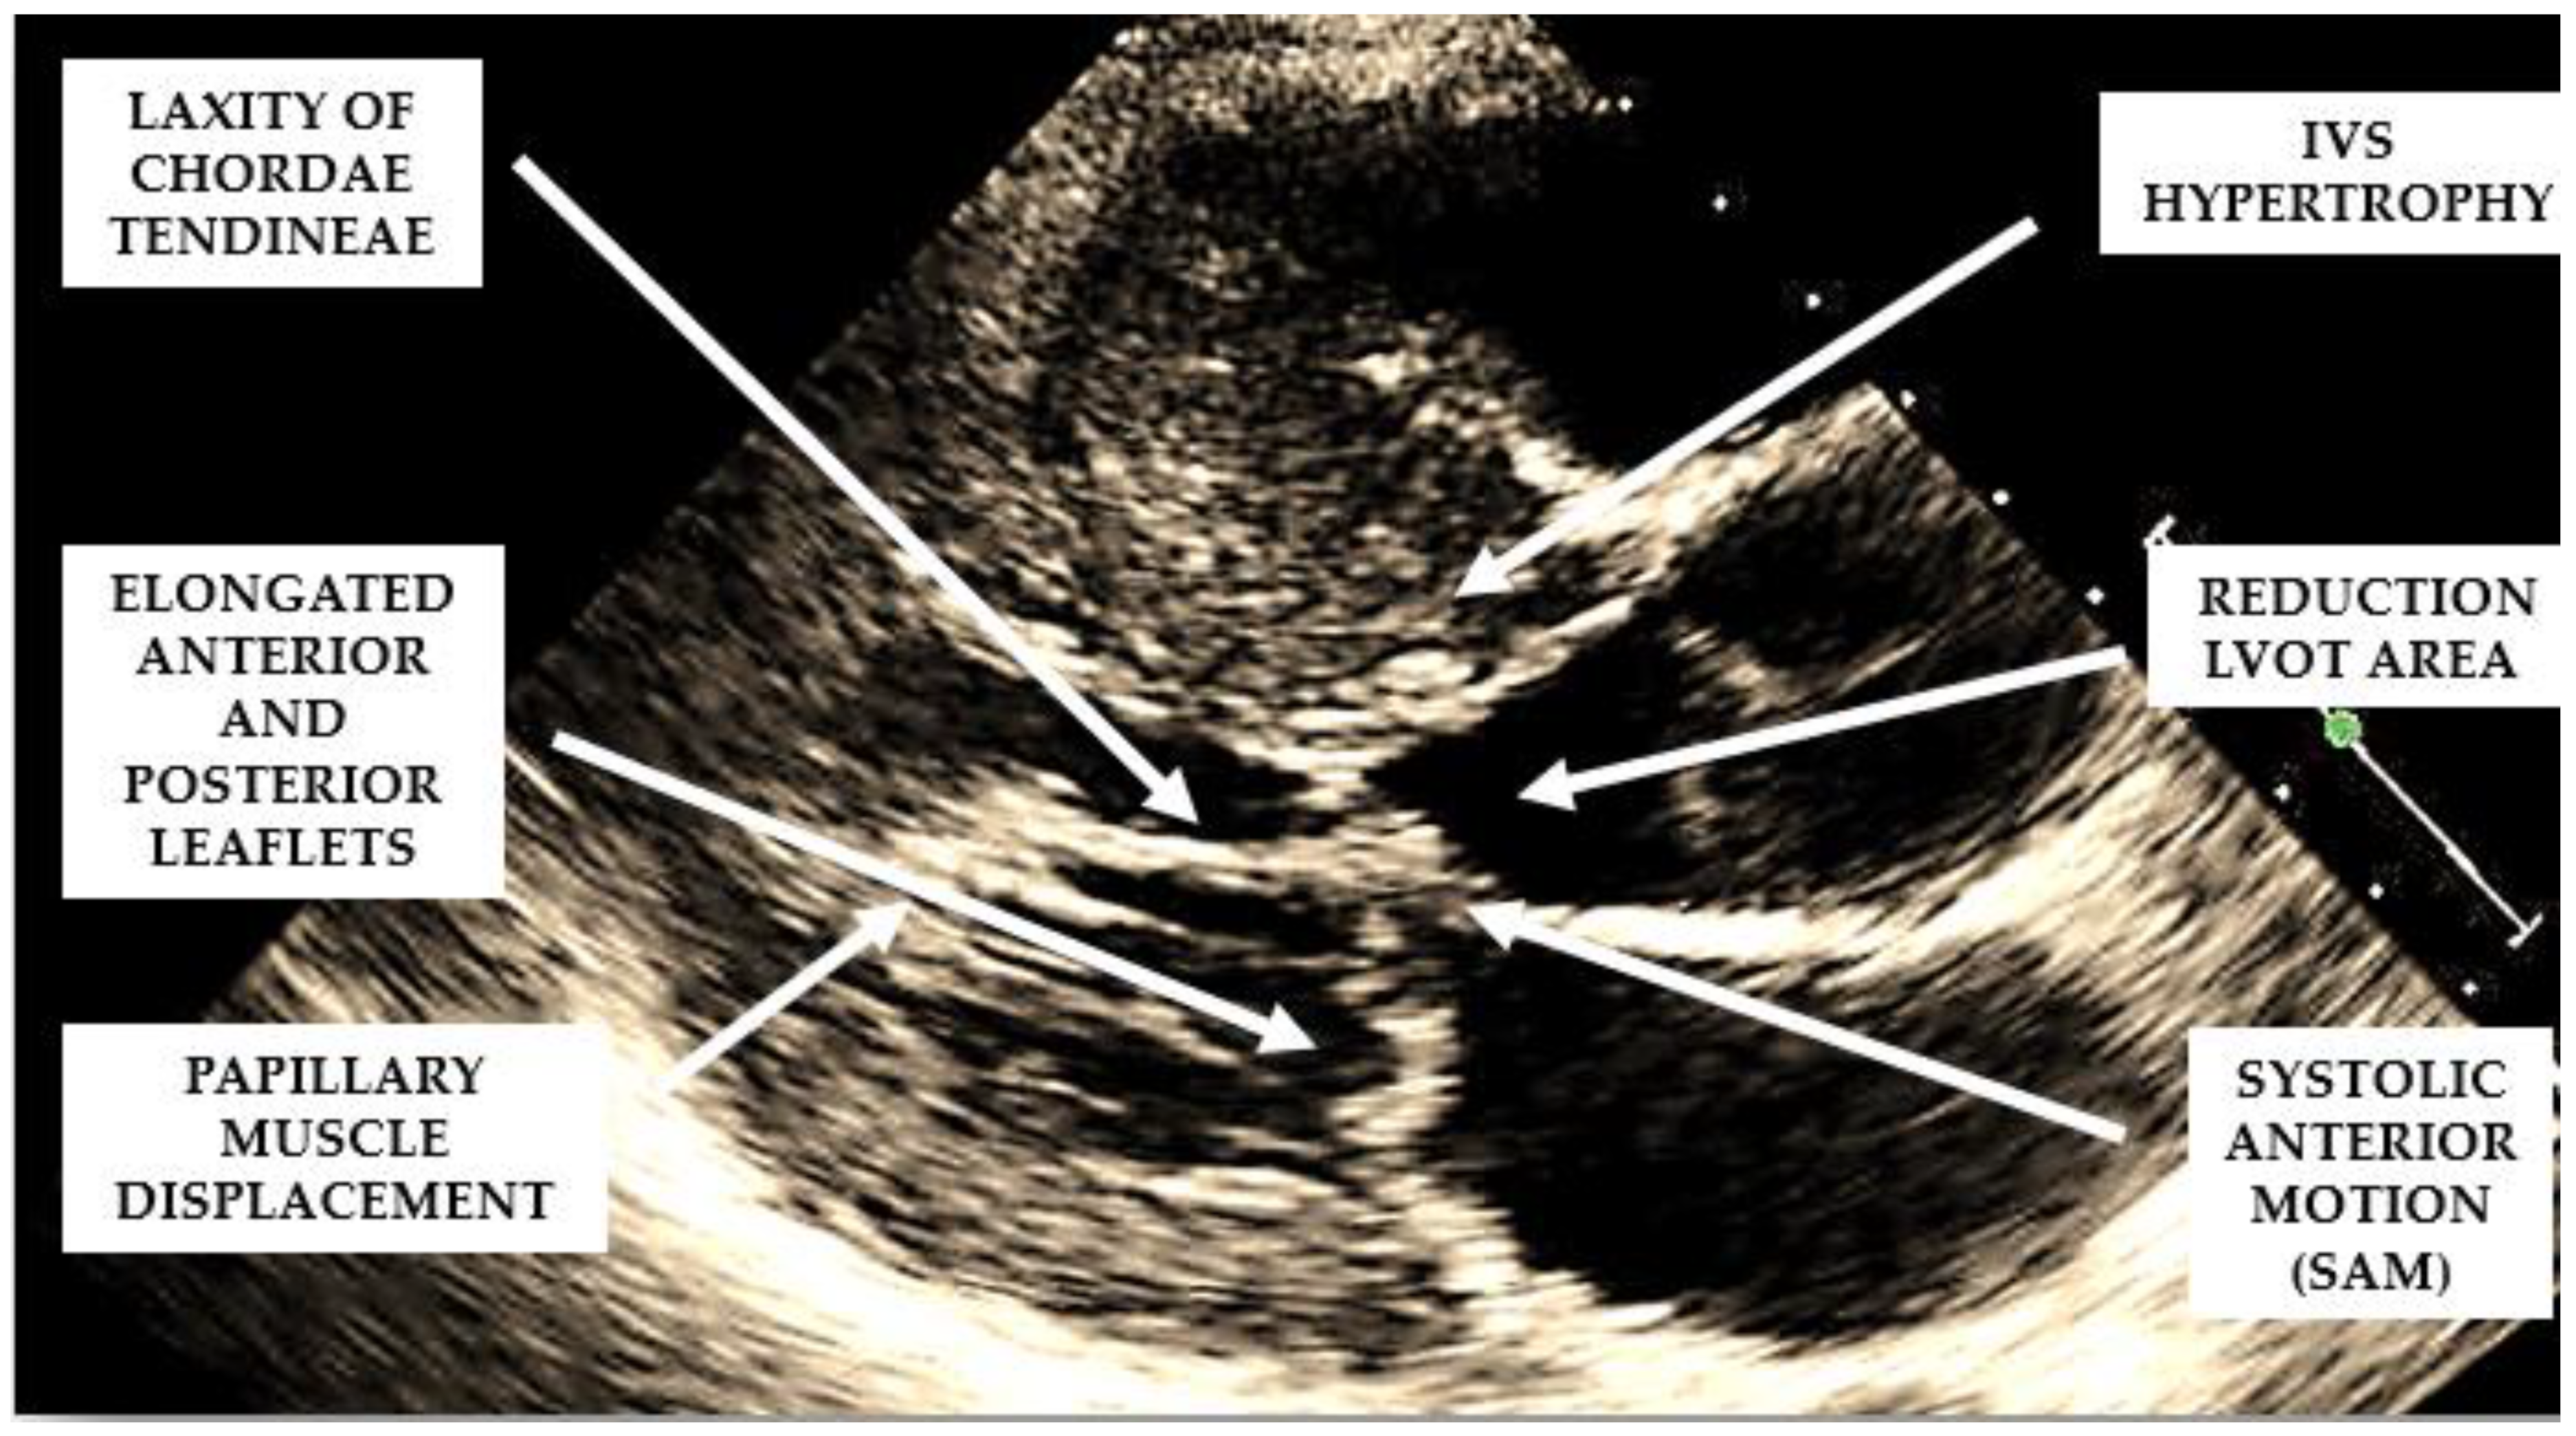

Figure 2. Mechanisms involved in the generation of left ventricular outflow tract obstruction in patients with hypertrophic cardiomyopathy.

Several structural and functional abnormalities of the mitral valve may substantially contribute to LVOTO. The increase in length of the anterior and/or posterior mitral leaflets [10,11] (Figure 2), forward displacement of the anterior papillary muscle, and laxity of the mitral valve chords (Figure 2) have been implicated in the anterior displacement of the coaptation line and in abnormal leaflet coaptation, characterized by a posterior leaflet coapting the mid-portion of an anterior leaflet, leaving its distal portion unsupported. This part of the leaflet causes dynamic obstruction, via a combination of suction, caused by the Venturi effect of the rapid flow in LVOT, and a dragging mechanism, caused by blood pushing the leaflet towards the septum (Figure 2).

These dynamic changes result in mitral systolic anterior motion (SAM), which contributes to both LVOTO and mitral regurgitation. SAM is a common but non-specific finding in HCM. In fact, alternative causes of SAM, independently of the presence of LV hypertrophy, are hypovolemia, inotropic drug use, small ventricles in normal or hypertensive individuals, and mitral valve surgical repair.

When evaluating the presence and severity of obstruction in HCM, a systematic assessment of all the components of the mitral valve apparatus via 2D echocardiography is required. This technique allows a visualization of the presence and distribution of LV hypertrophy, the presence of SAM, elongation of mitral valve leaflets, displacement of papillary muscles, laxity of tendon cords and LVOT diameter reduction (Figure 2). In addition, 2D echocardiography allows a diagnosis of MCO via the observation of a typical hourglass appearance of the LV due to systolic septal contact with the anterolateral wall, which induces sphincter-like cavity obliteration, creating two distinct (basal and apical) LV chambers (Figure 5). In addition, 2D echocardiography allows a visualization of the presence of an apical aneurysm and any thrombotic formation. In this setting, contrast echo may also be helpful for the correct diagnosis.